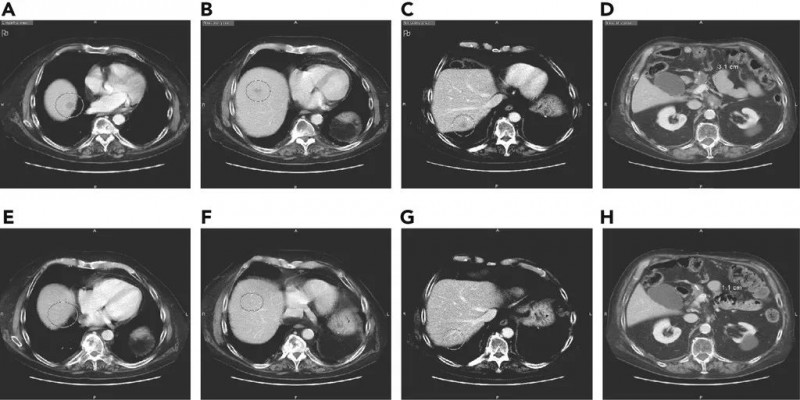

显然,疾病诊断越早,生存几率就越高。在可能的情况下,手术是目前为止最好的选择。PanCAN表示,及时被诊断患有胰腺癌的患者成为手术候选者,其存活时间是晚期的10倍。2017年发表在“外科肿瘤学年鉴”上的一项研究发现,肿瘤小于2厘米并通过手术切除的患者的5年存活率超过40%。